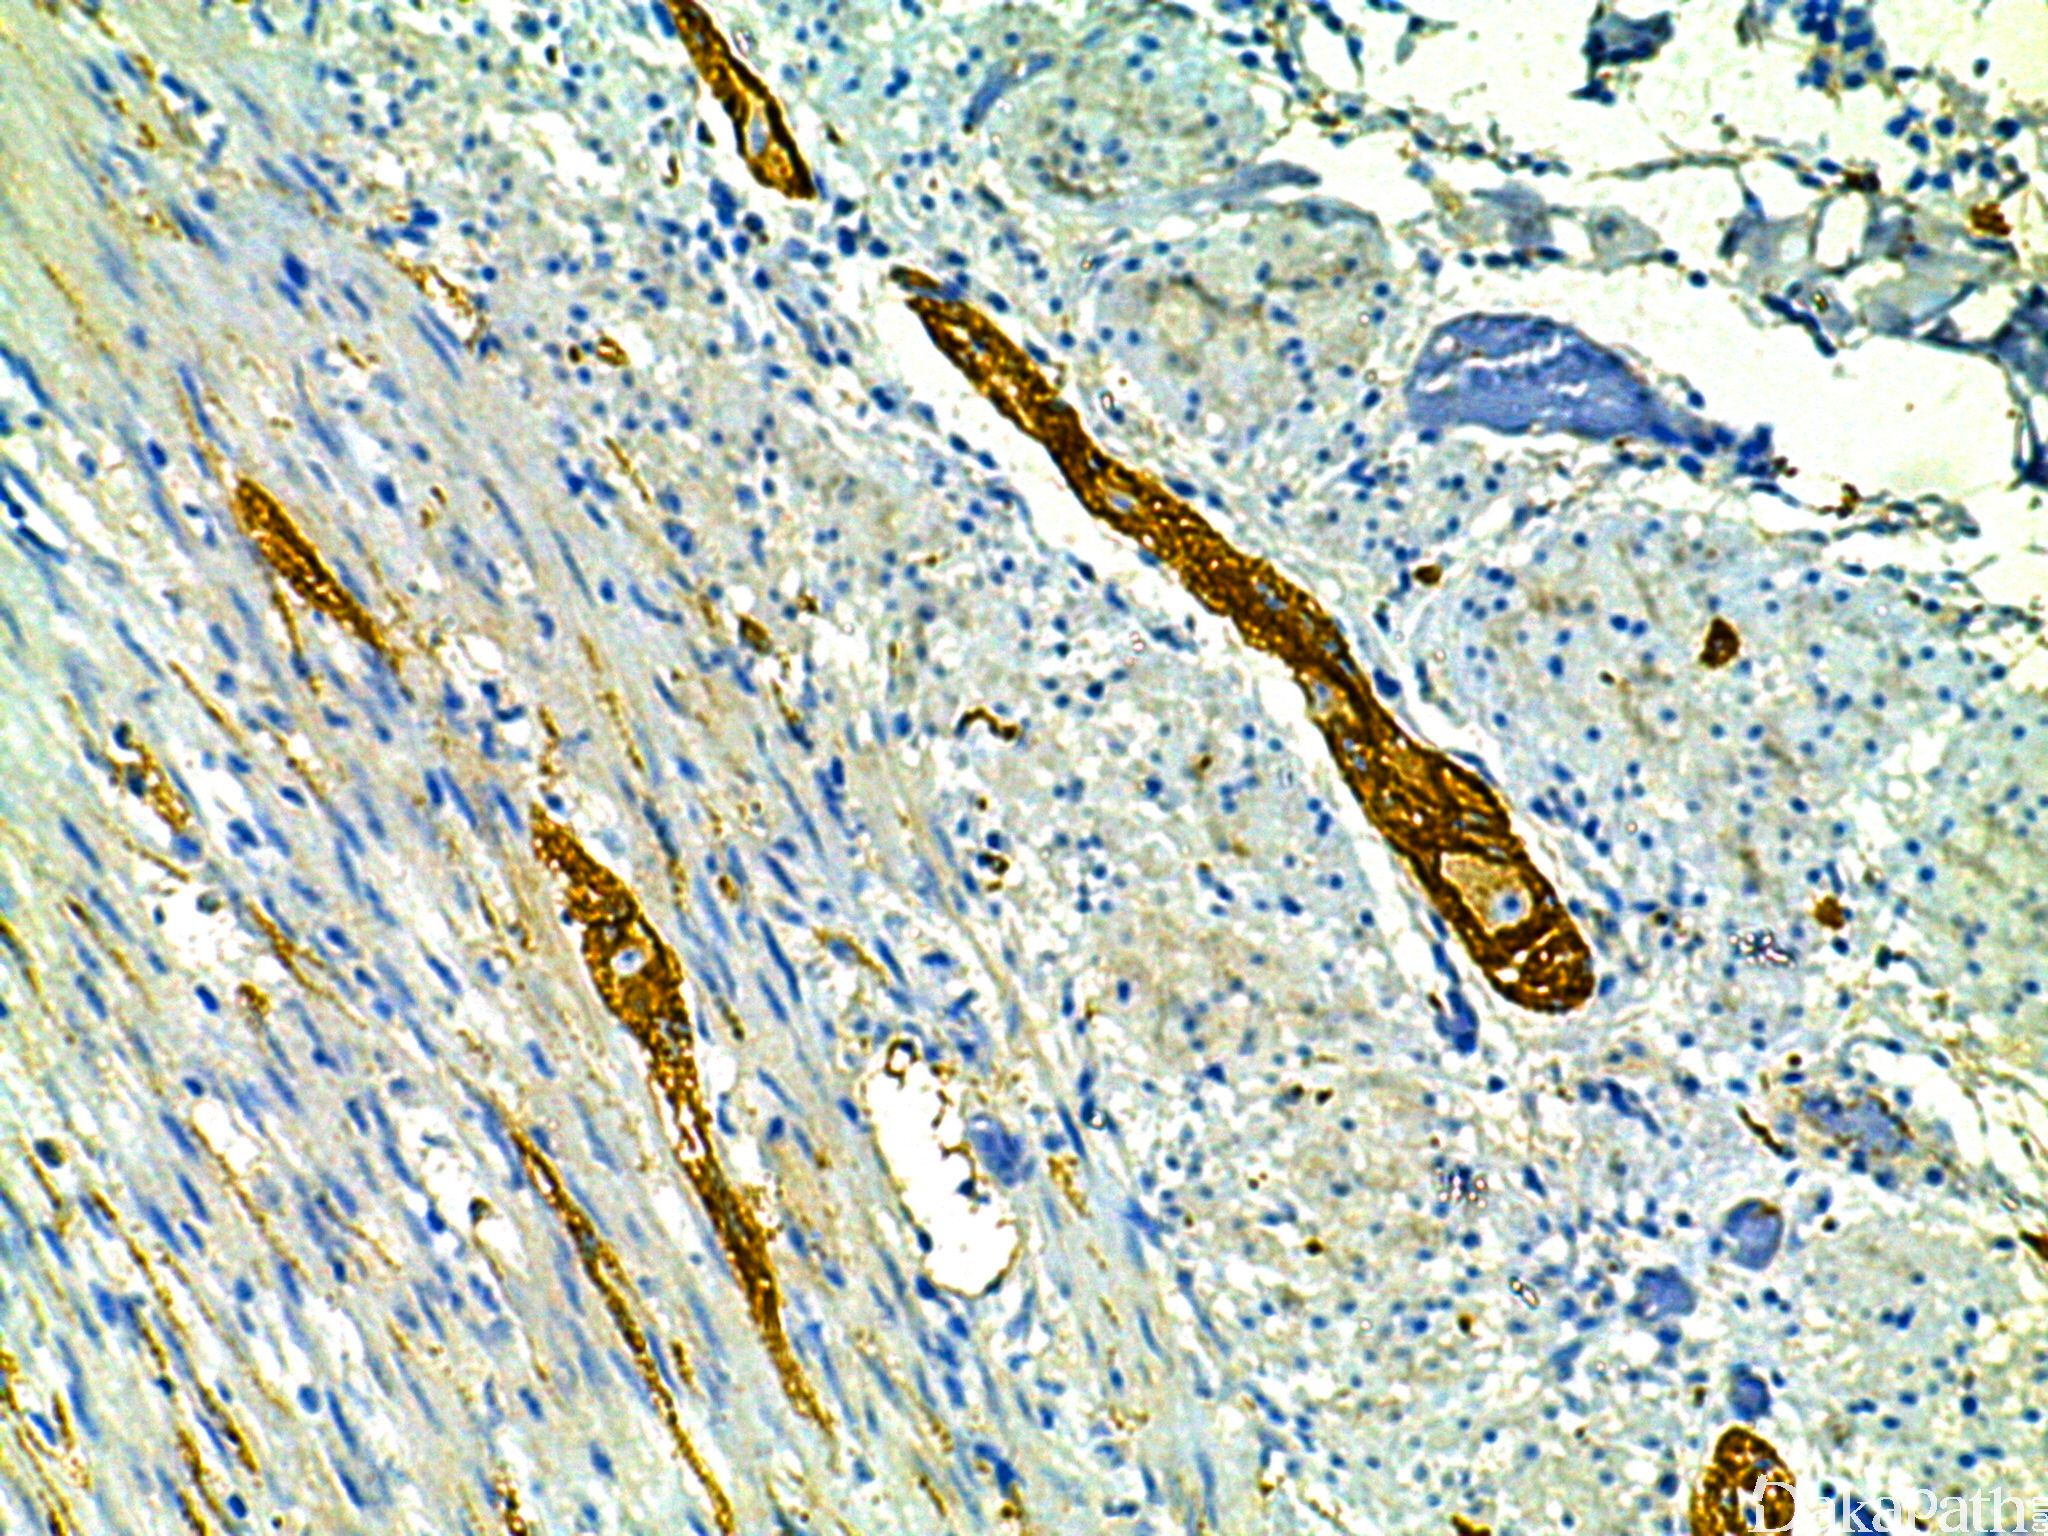

N-cadherin

神经钙黏附蛋白,Cadherin 家族成员之一,主要分布在神经组织、横纹肌、心肌组织中。

信号定位: 胞膜

在肿瘤中的表达情况:

几乎全部阳性(≥95%的病例阳性): 卵巢子宫内膜样癌、子宫内膜增生、乳头状肾细胞癌、卵巢低级别浆液性癌、脊索瘤、卵巢浆液性癌、卵巢浆液性囊腺瘤

通常阳性(<95%,≥75%的病例阳性): 间皮瘤,NOS、乳腺化生性癌、肾细胞癌、胰腺实性假乳头状肿瘤、胃肠道间质瘤、滑膜肉瘤,双向型、间皮增生、耳鼻喉神经内分泌癌、肉瘤样肾细胞癌

经常阳性(<75%,≥55%的病例阳性): 分泌性子宫内膜、上皮样间皮瘤、胆管癌、皮肤 Merkel 细胞癌

有时阳性(<55%,≥35%的病例阳性): 恶性黑色素瘤、上皮样肉瘤

少数阳性(<35%,≥15%的病例阳性): 胃腺癌,肠型、胃腺癌,弥漫性、梭形和上皮样细胞痣、深部韧带样纤维瘤病、上皮样血管肉瘤、卵巢黏液性癌、胰腺腺癌、滑膜肉瘤、乳腺髓样癌、肺腺癌、胰腺导管腺癌

偶尔阳性(<15%,≥5%的病例阳性): 透明细胞肉瘤、胆囊腺癌

几乎全部阴性(<5%的病例阳性): 肾嫌色细胞癌、恶性外周神经鞘膜瘤、上皮样血管内皮瘤、软骨肉瘤、腺泡状软组织肉瘤、上皮样外周神经鞘瘤、滑膜肉瘤,单向分化、卵巢黏液性交界性肿瘤/非典型增生性黏液性肿瘤、骨外黏液性软骨肉瘤、乳腺良性叶状肿瘤、卵巢黏液性囊腺瘤、壶腹腺癌、肾嗜酸细胞瘤